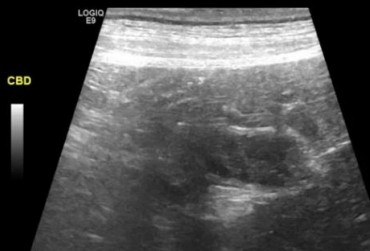

Pies, owczarek szetlandzki 6l. Mukocele. - 2

24 czerwca 2019

Wojciech Atamaniuk

Pies, owczarek szetlandzki 6l. Mukocele. - 1